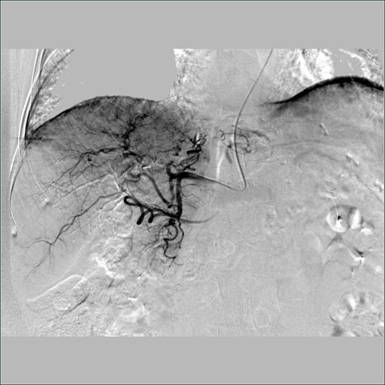

术中造影图片:

栓塞后图片: